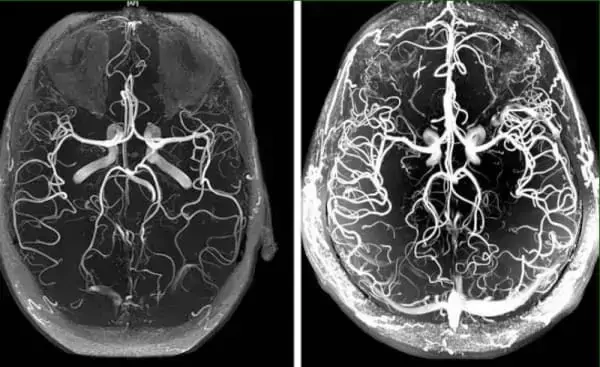

Ангиодистония сосудов головного мозга – это патологическое состояние, при котором нарушается тонус сосудов и нормальное кровообращение в тканях головного мозга. В этой статье вы сможете прочитать про её причины, механизмы и симптомы, при которых пора бить тревогу. А также про грозные осложнения этого коварного заболевания и про современный подход к лечению, доступный каждому.

Ангиодистония сосудов головного мозга влияет на работоспособность всего организма. Из-за неадекватного кровоснабжения мозга, снижается общая работоспособность, появляется слабость, а важные системы организма начинают работать со сбоями.